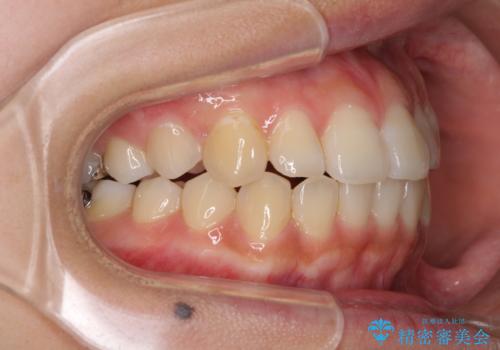

前歯の突出感とデコボコ インビザラインで改善

- 上下前歯のデコボコを気にして来院された患者様です。

インビザラインによる上下歯列の側方拡大と後方移動、IPR(歯と歯の間を削る)にるスペースの獲得により歯列を整えることとしました。

右上の小臼歯は歯根癒着をしており、様々な方法を試みるも動かすことができませんでした。

それでも奥歯のかみ合わせに不自由はなく、歯列をきれいに整えることができました。